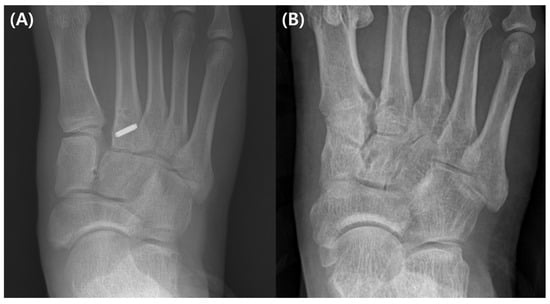

| C1–M2 | Medial cuneiform—second metatarsal bone damage with diastasis |

| C1–C2 | Medial cuneiform—intermediate cuneiform instability |

| C1–M1 | Medial cuneiform—first metatarsal bone instability |

| C2–M2 | Intermediate cuneiform—second metatarsal bone instability |